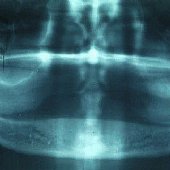

Bilder: Einzelimplantate im Bereich der Eckzähne

• Röntgenaufnahme des zahnlosen Unterkiefers.